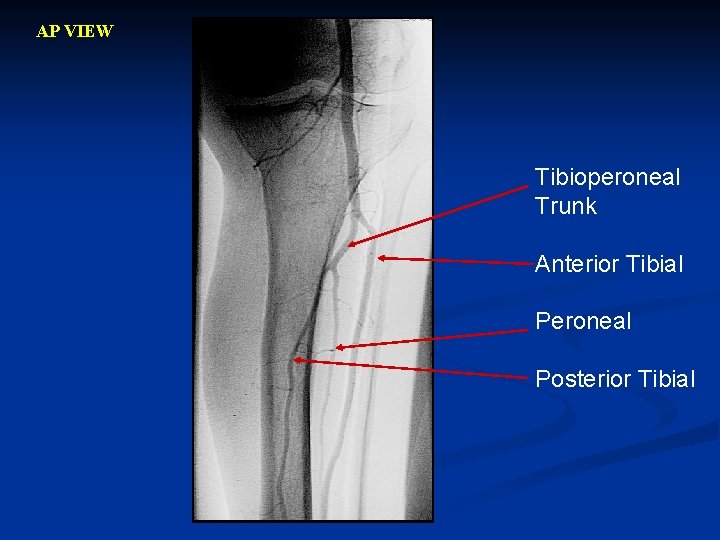

AP VIEW Tibioperoneal Trunk Anterior Tibial Peroneal Posterior Tibial